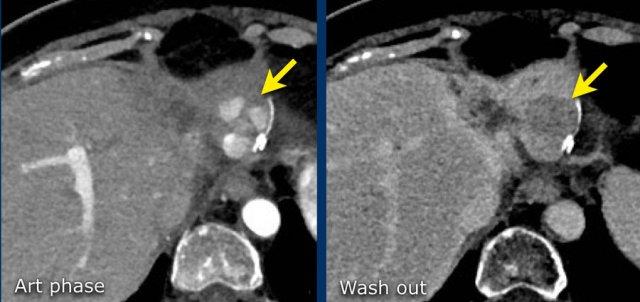

Đây là một bệnh nhân khác với tổn thương có ngấm thuốc và hiện tượng washout.

Lưu ý vỏ bao ngấm thuốc trên thì muộn.

Vỏ bao là một trong những đặc điểm chính của HCC và có thể hoàn toàn hoặc một phần.

Vỏ bao cần được tính vào trong phép đo kích thước của tổn thương.